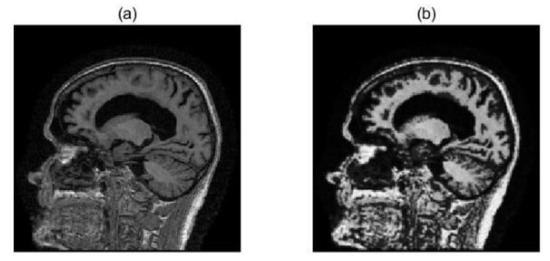

2.2. Image Preprocessing

2.3. Image Registration